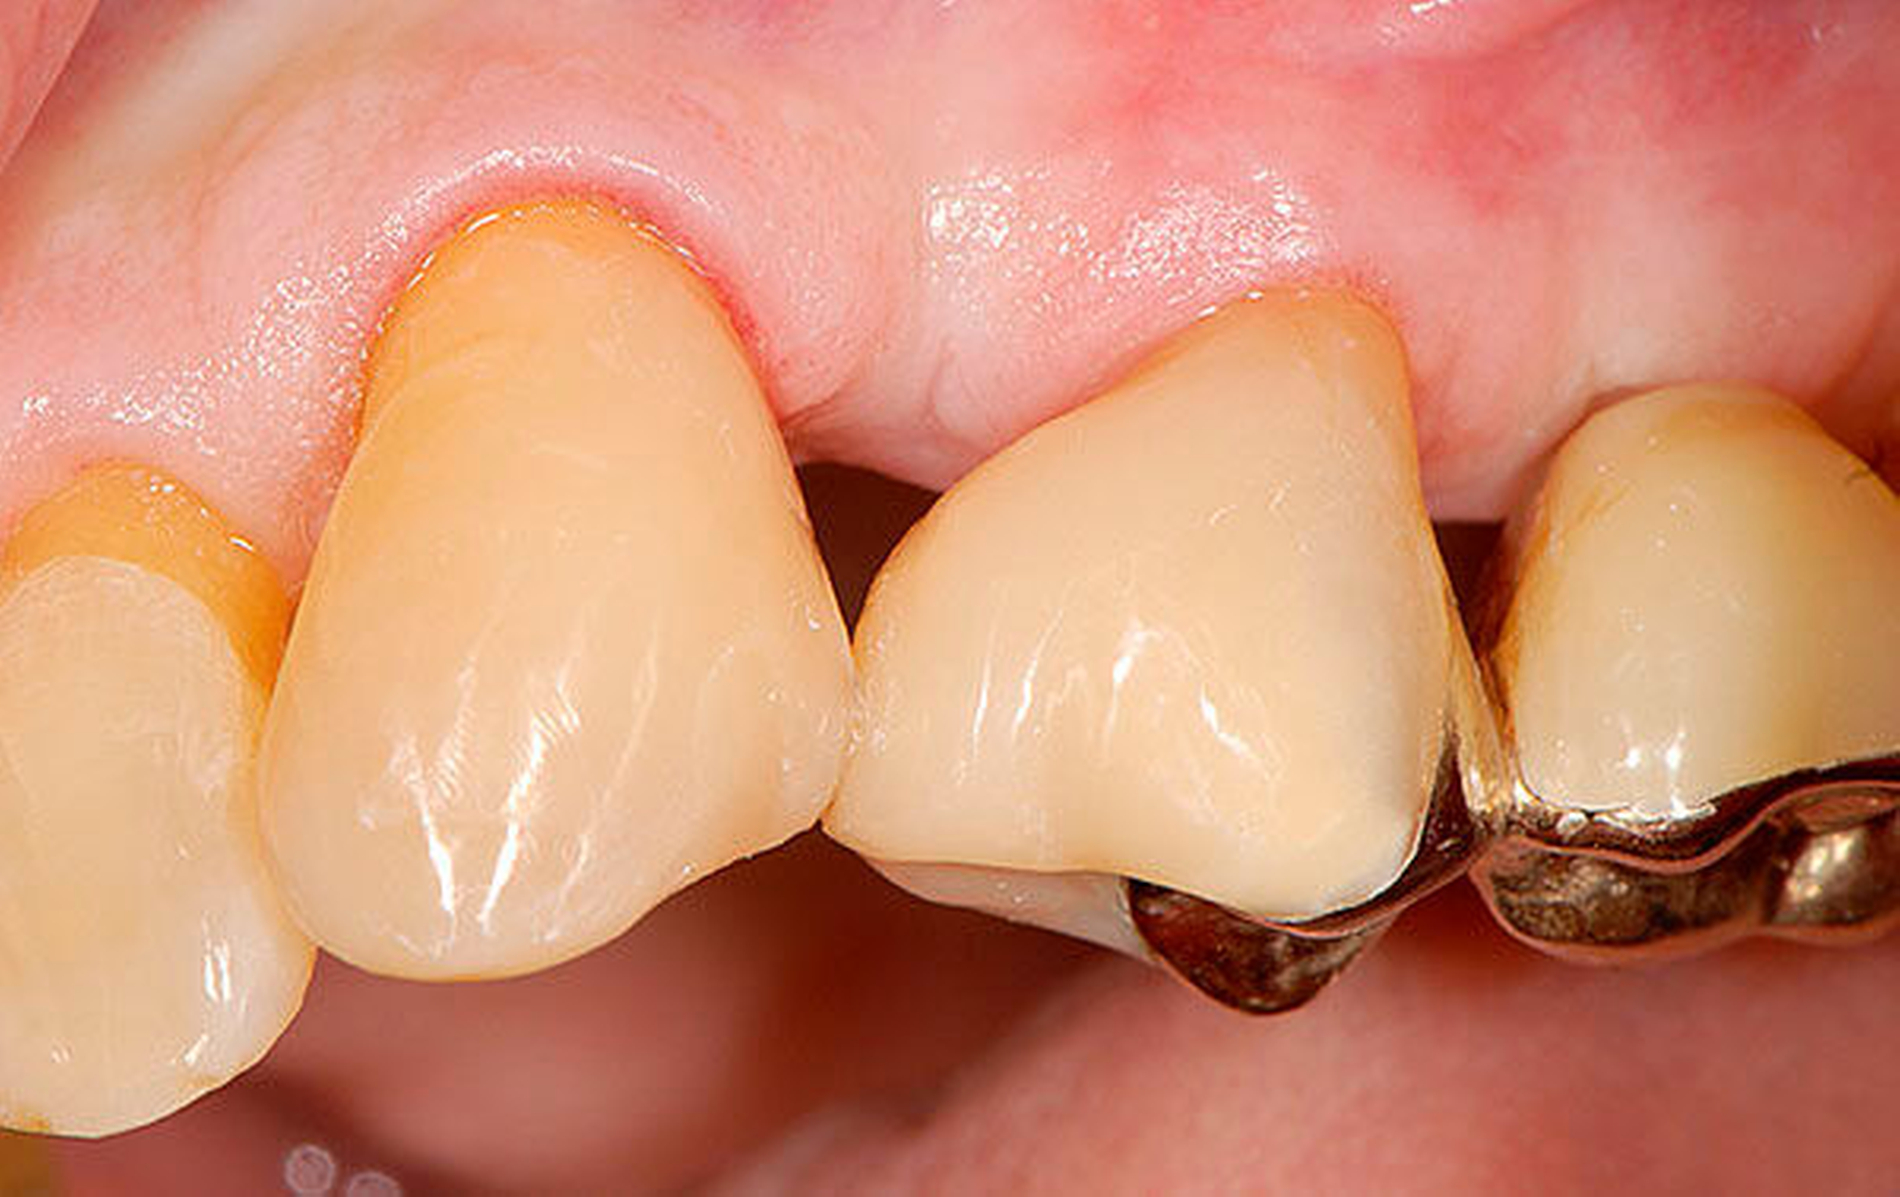

Senioren haben – wie oben ausgeführt – immer häufiger zahlreiche eigene Zähne. Im Fall von Lückenbildungen müssen diverse Behandlungsalternativen in Erwägung gezogen werden. Dazu zählen neben klassischen prothetischen und implantologischen Versorgungen auch andere Optionen (Tabelle 1). Nicht jede Lücke muss geschlossen werden. Wenn funktionell und ästhetisch keine relevanten Einschränkungen bestehen, kann auch ein Monitoring (Belassen und Beobachten) eine gute Lösung sein [Staehle, 2010; Listl et al., 2016]. Daneben kommen zuweilen Zahnumformungen und -verbreiterungen (Abbildung 1) oder direkte Freiendanhänger aus Komposit als Behandlungsmittel zum Lückenschluss in Betracht [Staehle, 2007, 2009, 2010, 2012, 2017; Staehle et al., 2014, 2015a, b; Frese und Staehle, 2018]. Schließlich ist für Patienten, bei denen aufwendiger festsitzender Zahnersatz nicht möglich ist und die keine herausnehmbare prothetische Versorgung wünschen, die Verfolgung des Prinzips der verkürzten Zahnreihe [Walter, 2016] zuweilen eine gute Alternative. Zur praktischen Realisierung dieses Konzepts kann heute die konservierend-restaurative Zahnheilkunde (zum Beispiel über Zahnverbreiterungen und -anhänger, eventuell in Kombination mit Schienungen) ebenfalls viel beitragen.

Abbildung 1 A-I: 84-jähriger Patient mit arterieller Verschlusskrankheit (Claudicatio intermittens)